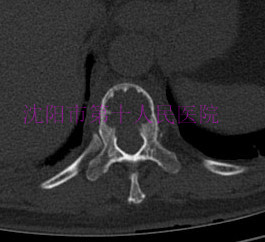

术前CT显示:胸11-12椎体骨质破坏,椎间死骨形成,病椎硬化,椎旁软组织肿胀。